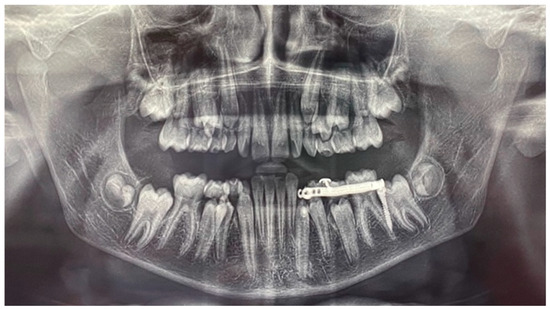

After 12 months, the mandibular canine (element 3.3) was disimpacted, in the axis with its eruptive path and with a correct eruption angle (Figure 13). The crown of the element was visible. The space present and the subject’s still-early mixed dentition was considered favourable to spontaneous eruption and the tooth was allowed to passively erupt. The disimpaction appliance was then removed and the miniscrew, still stable, was removed by unscrewing it.

The tooth element was followed over time through clinical monitoring every month and radiographic follow-up every 6 months (Figure 14).

Figure 13. Panoramic radiograph at the end of the orthodontic traction with the customized skeletal anchorage device.